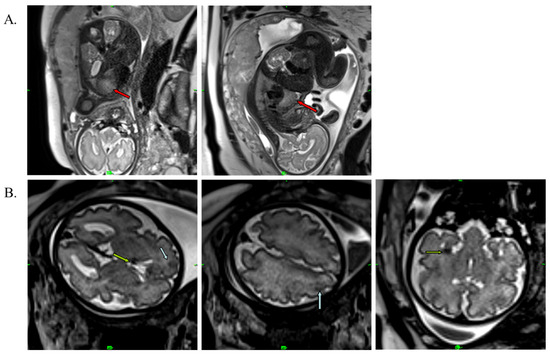

A medical team consisting of a cardiologist, clinical geneticist, obstetrician, and neonatologist decided to start oral immunosuppressant therapy for the mother (everolimus; Votubia). The goal of the treatment was to reduce the size of the rhabdomyoma, which lasted for five weeks. Oral everolimus was given daily. An initial dose of 10 mg/day everolimus was administered. The dose was adjusted to 5 mg/day from day 10 to set the 5–15 ng/mL target trough level (see Table S1). Blood values, including hemoglobin, leukocytes, leukocyte differentiation, thrombocytes, and CRP, were monitored during the treatment. All laboratory parameters were within the normal range. Everolimus reduced the size of the rhabdomyoma by almost half (20 × 20 × 33 mm) (Figure 3A). Everolimus was discontinued on day 36, two weeks before the scheduled cesarean section, to avoid complications and pre- and postnatal infection. The fetus and mother did not experience adverse events during the entire length of the treatment. Fetal MRI performed during the 38th week of gestation also revealed renal cysts in the fetus (Figure 3C).

Figure 3. T2-weighted MRI image of the fetus at the 38th week of gestation. (A) Red arrows show cardiac rhabdomyoma in reduced size (20 × 20 × 33 mm). (B) Blue arrows show cortical tuber in the gyral core (2), and green arrows represent subependymal nodule in the brain. (C) Purple arrow shows the renal cyst.